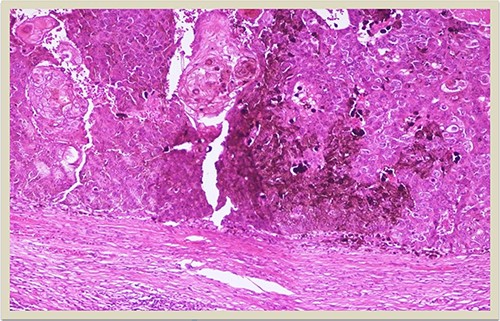

A 69-year-old man was admitted to our hospital with a nodular skin tumor of the back (Fig. 1). The patient had no ongologic history. We performed excisional biopsy that revealed collision tumor. The collision tumor consisted of mixed melanosquamous tumor (dermal squamomelanocytic tumor) together with BCC (Fig. 2). The BCC was superficial spreading. The mixed element contained squamous cell carcinoma of well/moderately differentiated and a neoplasm with melanotic characteristics, which due to cell atypia, presence of mitoses and high index of cell proliferation (Ki67: 80%) was described as melanoma (Fig. 3). Diagnosis of the melanotic and the squamous element was confirmed with immunohistochemistry (Figs 4 and 5).

H–E × 2: Collision tumor: in the right side of the photo is shown the dermal squamomelanocytic tumor component and in the left side the superficial basal cell carcinoma (H–E stain ×2 magnification).